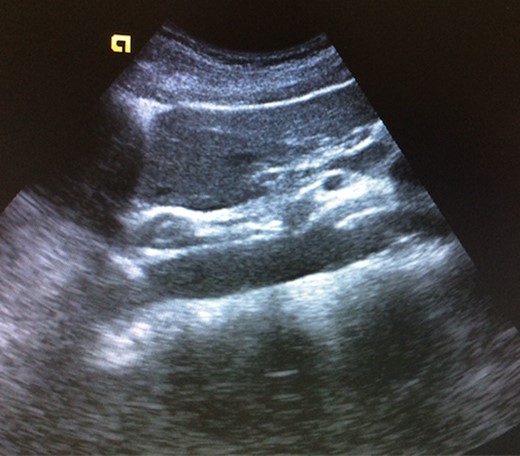

A 39-year-old Caucasian female patient presented to a General surgery outpatient clinic with complaints of epigastric pain, nausea, vomiting and weight loss for more than 5 years. The pain was worse after eating and with supine position. Vomiting was usually initiated 3–4 h after meals and consisted of undigested food. She had no significant prior medical history. On examination, the patient was extremely emaciated, with normal vital signs but with a distended abdomen and fullness over the epigastrium. She had already done an upper endoscopy that only showed gastric stasis. Abdominal ultrasound revealed a reduced angle between the AA and SMA (Fig. 1). An upper GI contrast study was requested, which revealed a distended stomach with delayed gastric emptying and lagging of contrast at the third portion of the duodenum (Fig. 2). Abdominal computed tomography (CT) scan was then performed. It demonstrated a severe distension of the stomach and proximal portions of the duodenum with constriction of the third part of the duodenum between the AA and SMA, with a reduced angle (11°) and shortened distance (4–5 mm) between these two arteries (Figs 3 and 4). These findings were suggestive of an aortomesenteric clamp. Hence, based on known findings, the diagnosis of Wilkie’s syndrome was established.

Abdominal ultrasound—reduced angle between abdominal aorta and superior mesenteric artery.